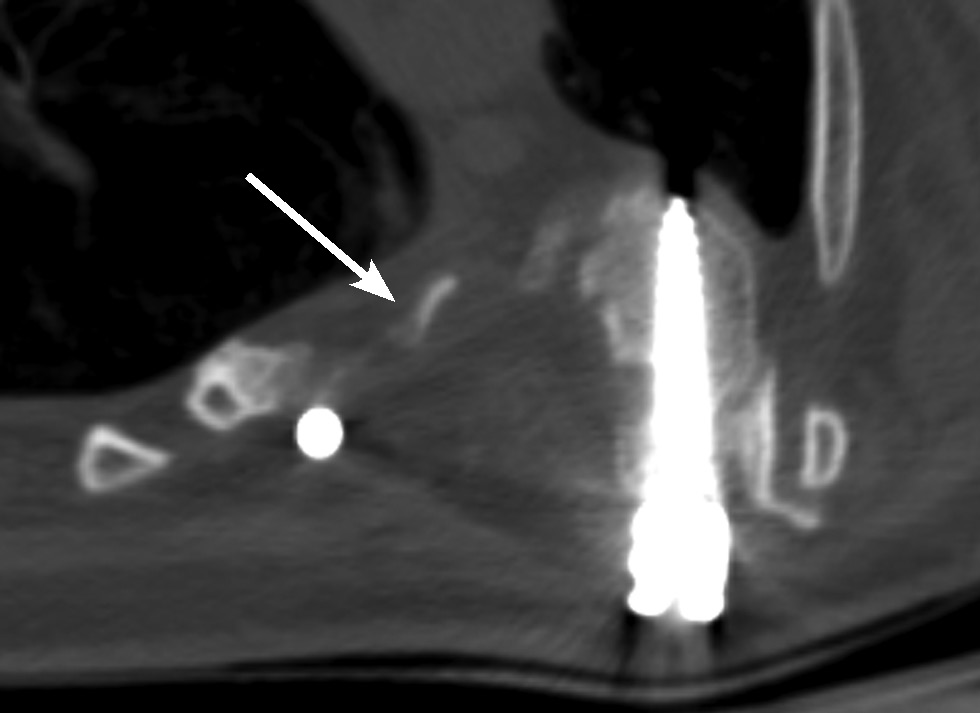

Учитывая клиническую картину и данные обследования, принято решение о проведении хирургического лечения с нейромониторингом. Осуществлена транспедикулярная фиксация позвоночника на уровне Th2–L2 без дополнительной коррекции (in situ). Выполнена ламинэктомия на уровне Th6–9, визуализированы дуральный мешок без пульсации и спинномозговые нервы на уровне Th6–9. Дуральный мешок и спинномозговые нервы распластаны и гипотрофичны, с синюшным оттенком. Визуально определяется сдавление дурального мешка на уровне Th6–9 позвонков по вогнутой стороне деформации, обусловленное ножками дуг позвонков. Высокоскоростным бором произведена частичная резекция ножек дуг на уровне Th6–9 позвонков справа. После проведённой резекции отмечается расправление дурального мешка. Выявлено натяжение дурального мешка, обусловленное корешком Th8 слева (на выпуклой стороне деформации). Произведена радикулотомия Th8 с выпуклой стороны деформации с целью мобилизации спинного мозга на данном уровне. После выполненной резекции ножек дуг Th6–9 и радикулотомии Th8 спинной мозг сместился к вогнутой стороне, приняв новое положение. Во вновь сформированном пространстве вокруг дурального мешка выявлено его плотное прилегание к рёберно-поперечным суставам и головкам рёбер на уровне Th7–8, что обусловливало его вторичную компрессию. Высокоскоростным бором произведена резекция рёберно-поперечных суставов и головок рёбер на уровне Th7–8 позвонков. Твёрдая мозговая оболочка расправилась, признаков компрессии нет. Пульсация удовлетворительная через 10 мин после его менинголиза. Далее выполнен задний спондилодез костными аутотрансплантатами, рана промыта и ушита с установкой раневого дренажа (рис. 10).

Рис. 10. Компьютерная томография позвоночника на третьи сутки после операции. Аксиальная проекция на вершине деформации (уровень Th8). Стрелкой указана зона декомпрессии: резецированная ножка дуги позвонка Th8 с рёберно-поперечным суставом и головкой ребра.

Fig. 10. Computer tomography of the spine on the third day after surgery. Axial projection at the apex of the deformity (Th8 level). The arrow indicates the decompression zone: the resected pedicle of the Th8 vertebral arch with the costotransverse joint and the head of the rib.